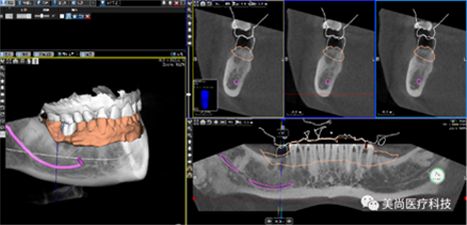

即以患者CT影像信息为基础,借助专用种植设计软件,进行术前诊断和种植模拟设计,通过种植手术导向模版(简称导板),将术前制定的种植方案应用于种植手术和修复的全过程,实现以修复为导向的牙种植技术。

方案设计(利用专用的种植设计软件完成)

A.将CBCT数据导入软件中

B.绘制下颌神经管

E.软件上修复体设计

C.添加模型数据

D.图像拟合

F.选择牙位添加种植体

G.选择合适的导环全程或者定位完成植体设计

H.自动生成种植计划报告